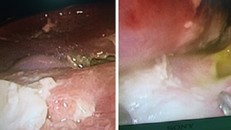

Hiện nay tình trạng viêm dạ dày ở trẻ em ngày càng tăng, nguyên nhân là do thói quen ăn uống, vừa xem tivi hay điện thoại vừa ăn, thức khuya chơi game, stress học tập… Có trường hợp trẻ mới 5 tuổi đã mắc bệnh dạ dày.